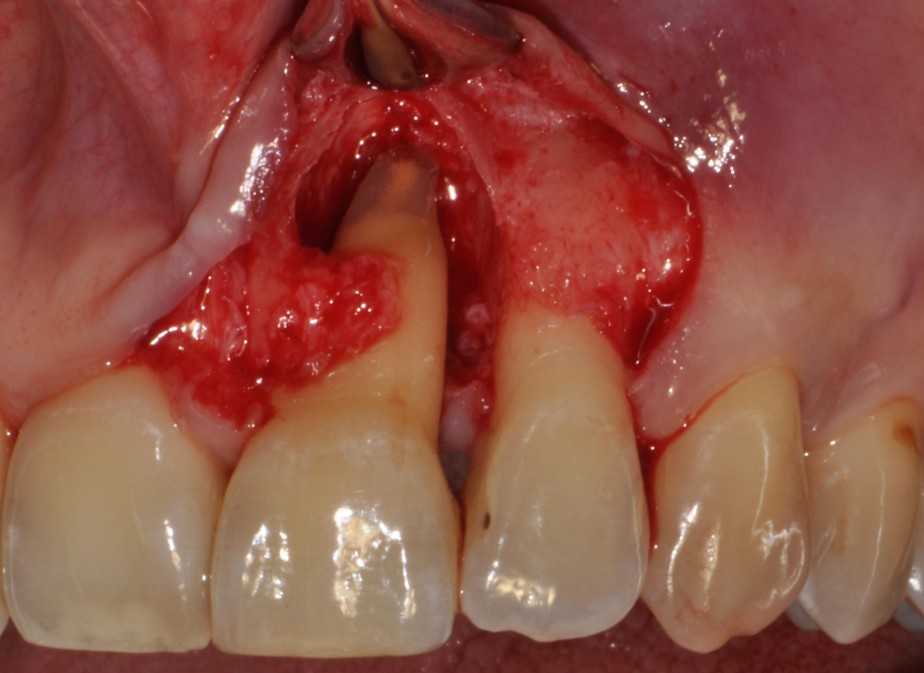

Nowadays, periodontal regenerative surgery has clearly demonstrated its ability to significantly improve the prognosis of teeth that were previously considered hopeless, particularly in the management of infrabony defects. Growing evidence further indicates that regenerative surgical approaches provide superior clinical outcomes compared with open flap debridement alone, not only in infrabony defects, but also in suprabony defects and furcation involvements.

This workshop will explore the biological rationale, clinical decision-making, and surgical techniques involved in periodontal regeneration. While the primary focus will be on the regenerative management of infrabony defects, the discussion will be extended to more complex defect configurations. Particular emphasis will be placed on defect morphology, as well as on the selection of biomaterials and surgical approaches that critically influence clinical outcomes.

Key topics will include flap design, papilla preservation strategies, wound stability, soft tissue management, post-operative care, as well as the limitations and challenges of periodontal regeneration. Even in complex periodontal defects, a sound biological and clinical rationale for reconstruction and regeneration can often be identified.